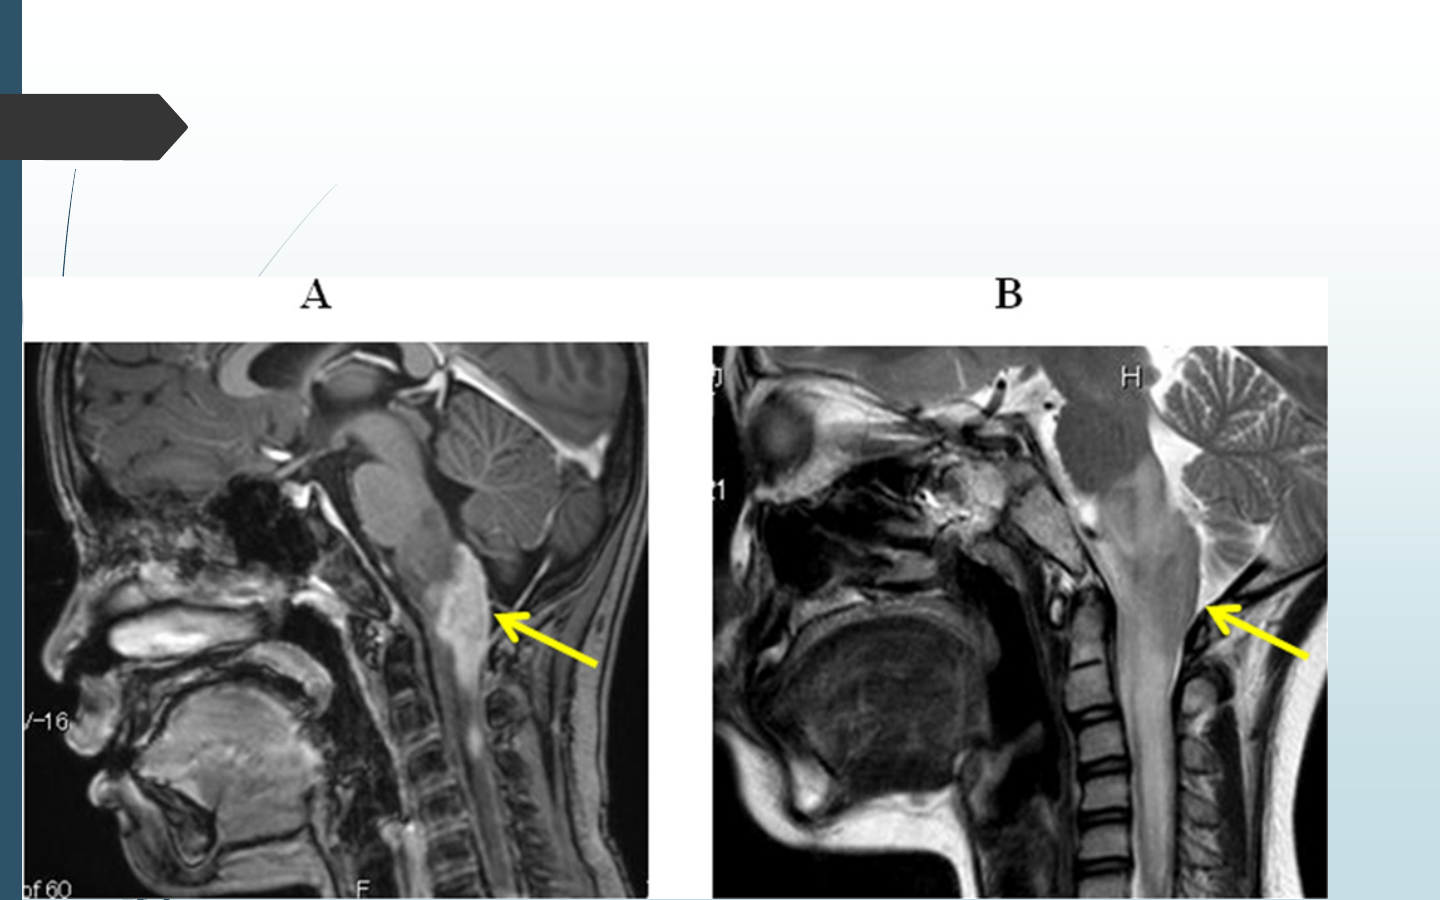

Causesneurologiques:seméfier(HTIC,pathologiede

lafossepostérieure,TC…)